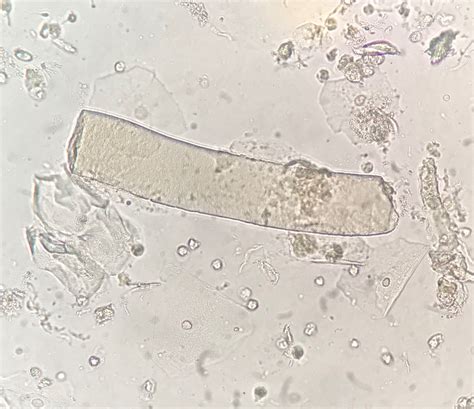

Waxy cast urine, also known as waxy casts, is a medical condition that can indicate various underlying health issues. These casts are cylindrical structures composed of Tamm-Horsfall protein, which are typically found in the urine of individuals with certain kidney disorders. Understanding the causes, symptoms, and treatment options for waxy cast urine is crucial for early detection and effective management of related conditions.

Waxy cast urine refers to the presence of waxy casts in the urine. These casts are formed when Tamm-Horsfall protein, a glycoprotein produced by the kidney's distal tubules, becomes trapped in the urine. The waxy appearance is due to the protein's ability to harden and form a cylindrical shape. Waxy casts are often associated with chronic kidney disease and other renal disorders.

• Urinalysis: A urine test can detect the presence of waxy casts and other abnormalities. The urine sample is examined under a microscope to identify the type and number of casts.